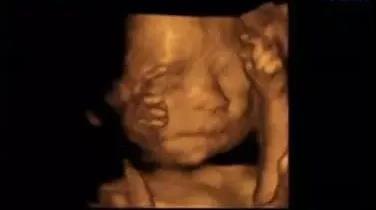

在活动期间内,凡是在雅安恒博医院做四维/5D彩超的孕妈们,可选一张宝宝最萌萌哒的四维/5D彩超照发到朋友圈,并邀请朋友们为萌萌的他/她点个赞。

福利二:四维/5D彩超晒照集赞有礼